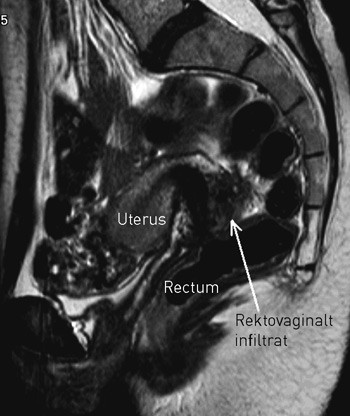

Ved dyp endometriose har pasienten i tillegg til smerter ofte tarm- og blæresymptomer, eventuelt også menstruasjonsrelaterte blødninger fra henholdsvis tarm eller urinblære. Lokale forandringer i øvre del av vagina kan påvises ved inspeksjon, og dyp endometriose kan oftest diagnostiseres eller mistenkes ved palpasjon og vaginal ultralydundersøkelse. Mer nøyaktig diagnose og evaluering av sykdommens utbredelse før behandling oppnås ved MR-undersøkelse av bekkenet (fig 4), eventuelt supplert med spesifikke tarmundersøkelser (endoskopi, dobbeltkontrastrøntgen av colon, CT-kolografi) eller undersøkelser av urinveiene (cystoskopi, urografi).